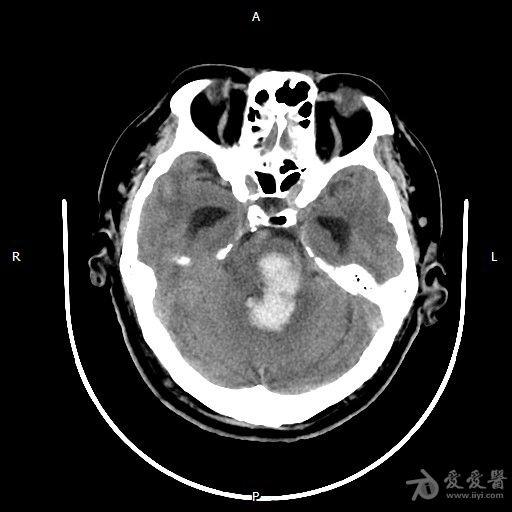

(10月13日晚,头部ct提示患者脑干出血10毫升.

我院重症医学科成功救治一例大面积脑干出血患者

行头颅ct检查提示:脑干出血,量约8ml.